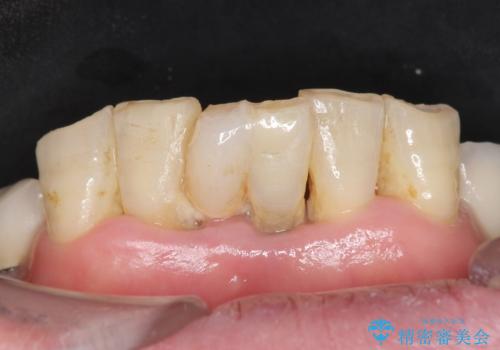

- 上下の前歯が抜けそうだとのことで来院されました。

精査したところ、動揺の著しい上下の前歯は重度の歯周病により保存不可能と判断しました。

ブリッジ、インプラント、義歯の選択肢の中で上下前歯ともにブリッジをご希望されました。

抜歯後歯肉の治癒を十分に待ったのち、ブリッジによる補綴治療を行いました。

上の前歯の再根管治療もおすすめしましたが、必要性を感じないとのことで土台のやりかえだけをご希望されました。